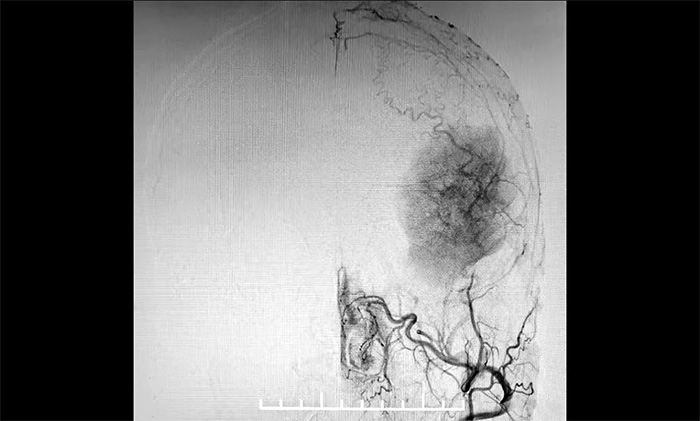

發(fā)生于額顳部位的巨大腦膜瘤,治療方法主要為顯微外科手術(shù)切除。該腫瘤不僅體積巨大,橫跨多個(gè)重要腦功能區(qū),行DSA檢查發(fā)現(xiàn),腫瘤包裹纏繞多根重要的動(dòng)脈血管,血供十分豐富。若直接行手術(shù)切除腫瘤,容易因術(shù)中大出血而危及患者生命。

▲ DSA檢查示:腫瘤血供豐富

大家一致認(rèn)為,患者手術(shù)指征明確,未見(jiàn)明顯手術(shù)禁忌。由于該腫瘤血供豐富,宜采取“術(shù)前栓塞+腫瘤切除”的方案,以減少術(shù)中出血,利于腫瘤完整切除,盡可能避免意外發(fā)生。

4A病區(qū)醫(yī)生團(tuán)隊(duì)與患者和家屬充分溝通,明確手術(shù)方案的必要性和風(fēng)險(xiǎn)性,并獲得充分理解、簽字同意后,11月23日,醫(yī)院學(xué)術(shù)副院長(zhǎng)兼神經(jīng)內(nèi)科4A病區(qū)主任席剛明教授在4A病區(qū)副主任王貴平博士及介入團(tuán)隊(duì)協(xié)助下,首先為患者在全麻下行腦血管造影+腦膜瘤栓塞手術(shù)。手術(shù)過(guò)程順利,復(fù)查腫瘤供血血管基本不顯影,為下一步進(jìn)行腫瘤切除創(chuàng)造了有利條件。